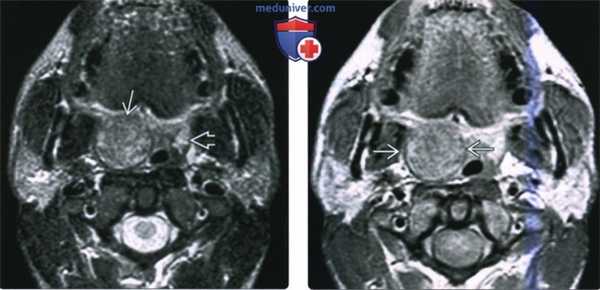

3. МРТ при неходжкинской лимфоме слизистого пространства глотки:

• Т1ВИ:

о Новообразование СПГ, интенсивность сигнала равна интенсивности сигнала от мышечной ткани

• Т2ВИ:

о Интенсивность сигнала варьирует и зависит от плотности клеточного строения, обычно однородный сигнал умеренной интенсивности:

- При повышенной целлюлярности сигнал на Т2ВИ менее гиперинтенсивный

о Нередко распространяется на окружающие структуры, в том числе основание черепа, окологлоточное пространство, пред-позвоночные мышцы

• ДВИ: диффузия ограничена, особенно при лимфомах, накапливающих ФДГ

• Т1ВИ с КУ:

о Новообразование глоточной, небной или язычной миндалины, накапливающее контрастное вещество

о Внутренние перемычки, накапливающие контраст, которые встречаются при гиперплазии миндалин или их воспалении, отсутствуют

(Слева) МРТ Т2ВИ FS МРТ, аксиальная проекция, на которой визуализируется неходжкинская лимфома правой небной миндалины, контуры образования четкие. Поскольку с возрастом объем лимфоидной ткани снижается, небольшой размер левой небной миндалины является нормой. Плоскоклеточный рак или доброкачественная смешанная опухоль могут выглядеть идентично, и только биопсия позволит установить диагноз лимфомы.

(Справа) МРТ Т1ВИ с КУ, аксиальная проекция, тот же пациент. Лимфома однородно накапливает контрастное вещество. При воспалении миндалины контраст бы накапливался отдельными полосами, в случае интра-тонзиллярного абсцесса в центре образования обнаруживается очаг некроза.